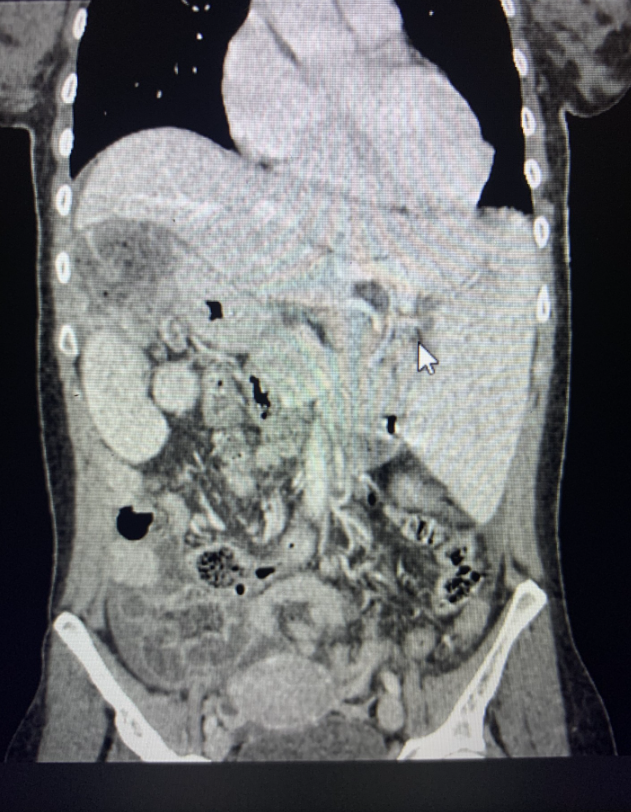

TAC Abdominal: Situs inverso de órganos intraabdominales. Imagen hipodensa de aspecto pseudocoleccionado subdiafragmático derecho de 89 x 63 mm, asociado a aumento de densidad y trabeculación de la grasa adyacente, que no consigue caracterizar por completo. Leve engrosamiento parietal hipodenso segmentario del colon izquierdo, asociado a aumento de densidad y trabeculación de la grasa adyacente, altamente sugestivo de colitis, de etiología indeterminada. Presencia de líquido libre en ambas gotieras y en pelvis.

Juicio clínico: Situs inverso de órganos intraabdominales y masa subdiafragmática.

Diagnóstico diferencial: vólvulo, desplazamiento por masa o megavíscera abdominal, situs inverso total.

Paciente intervenida por infarto de bazo superior y hemoperitoneo de 450 cc.

Esplenectomía de bazo superior con evolución favorable.